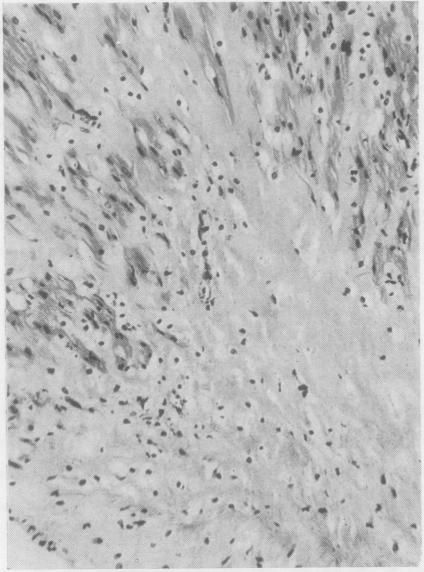

The pathology and chemistry of a case of gargoylism.

J Clin Pathol. 1956 Nov;9(4):305-15. doi: 10.1136/jcp.9.4.305.